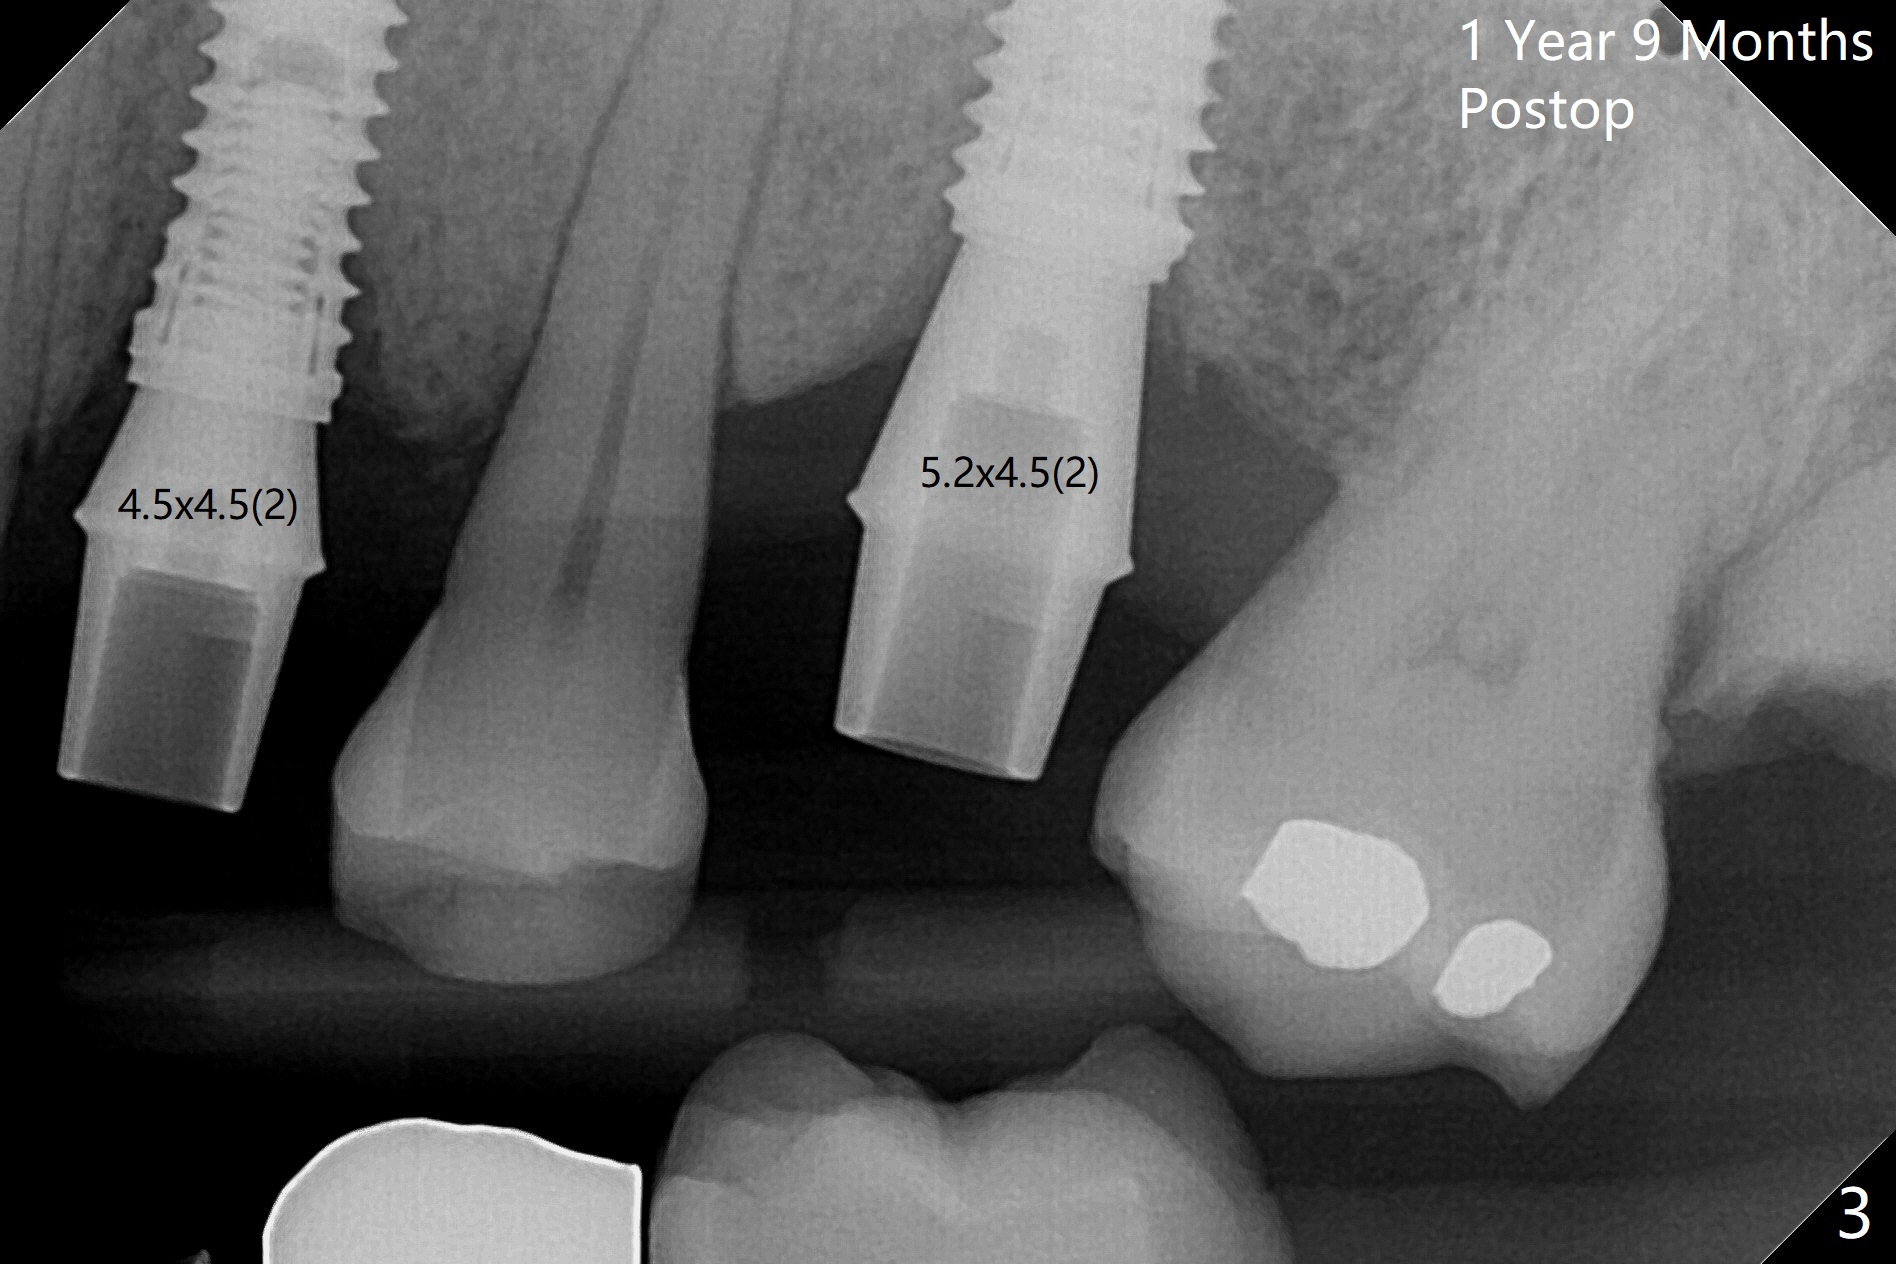

To remove the subgingival residual root of the tooth #12, buccal flap is raised, which provides access to see thread formation in the coronal portion of the socket following use of cortical tap. Bone harvested from osteotomy is placed in the remaining buccal socket (Fig.1). Bone density is so high at #21 that 4.5x8.5 and 4.5x10 mm drills are used before placement of a 4.5x10 mm with 12 mm offset in addition to use of cortical tap and back up of the implant several times (Fig.2).